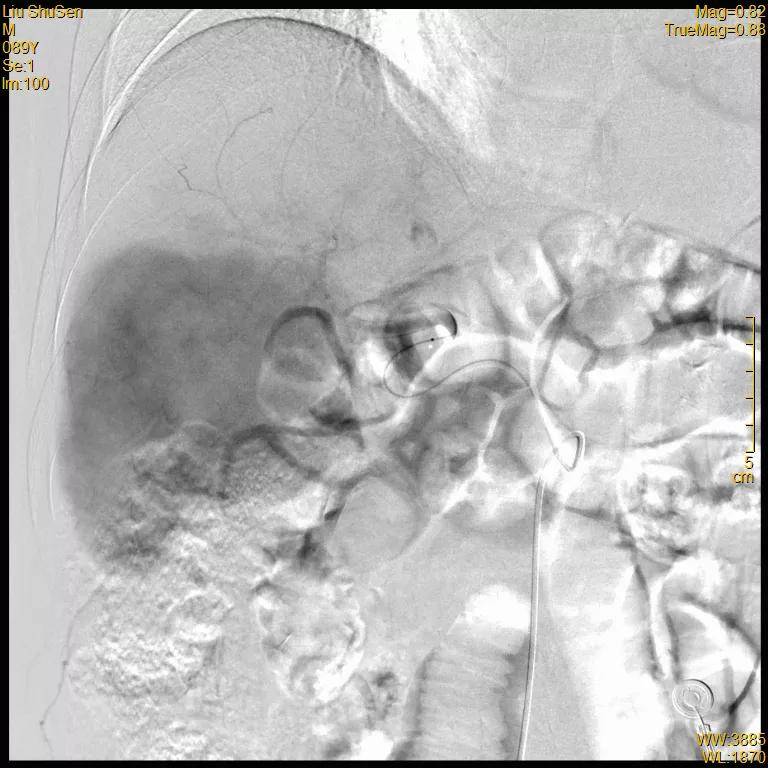

2020-12-15 术前MR增强

2020-12-15 术前MR冠状位

经过详细检查 , 患者甲胎蛋白升高 , 腹部MR增强示肝脏肿物 , 铅球样大小 。 诊断为原发性肝癌(BCLC B期) , 伴肝硬化 。